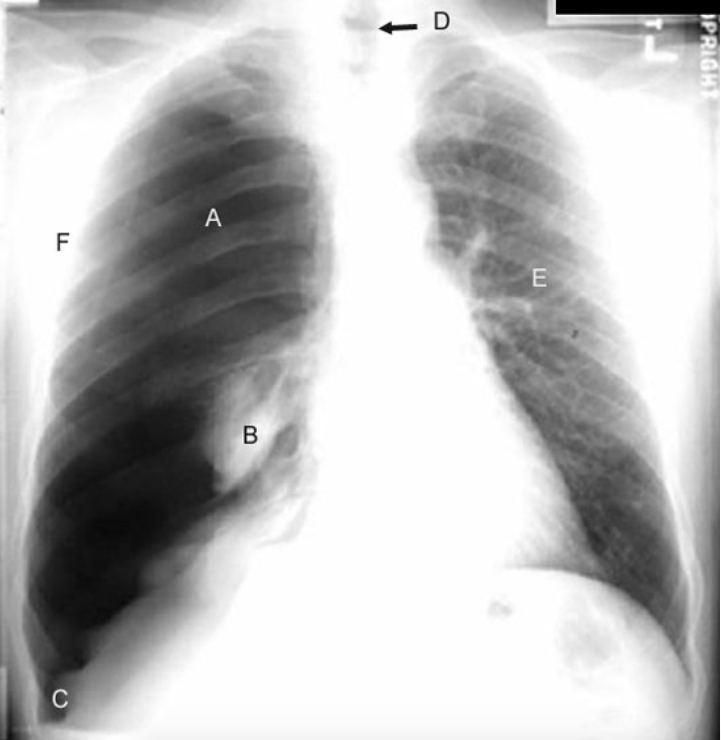

Identify A trhough F

Shift of mediastinum (D) to opposite side.

Deep sulcus sign (C).

Opposite lung (E): The vascular markings are prominent.

Larger hemithorax compared to opposite side. Hemithorax is in TLC position due to loss of negative pressure in the pleural space. (F)